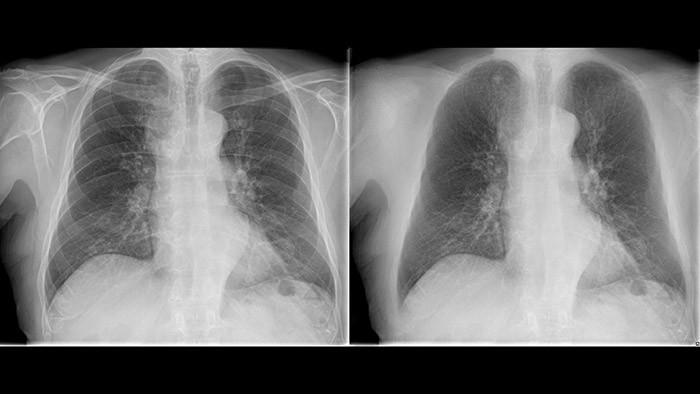

Philips Bone Suppression* ist eine innovative Technologie zur Bildoptimierung, die darauf ausgelegt ist, durch die Unterdrückung von Knochenstrukturen auf digitalen Bildern mehr Bildklarheit bei Thorax-Röntgenaufnahmen zu erhalten. Sie ist in den neuesten DigitalDiagnost C90 integriert und ermöglicht Weichgewebeaufnahmen bei digitalen Thorax-Röntgenaufnahmen.

Bone Suppression liefert neben der klassischen Thoraxaufnahme eine Weichgewebeaufnahme und unterstützt so ohne Erhöhung der Strahlendosis oder weiteren Zeitaufwand die Entscheidungsfindung des Radiologen. Mit Bone Suppression wird die Erkennung von abklärungsbedürftigen Lungenrundherden um bis zu 16,8 % verbessert.**